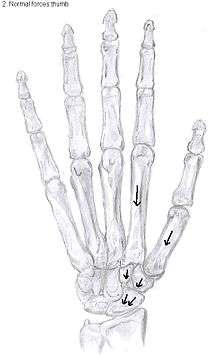

Trapeziectomy

The most simple form out of the four variations is the trapeziectomy alone, also referred as the simple trapeziectomy.[34] During this procedure, the trapezium bone is removed without any further surgical adjustments.

The trapezium bone will be removed through an approximately three centimeter long incision along the lateral side of the thumb. To preserve surrounding structures, the trapezium bone will be removed through fragmentation of the bone (the bone will therefore be broken into pieces).

An empty gap is left by the trapeziectomy and the wound is closed with sutures. Despite this gap, no significant changes in function of the thumb are reported.[33] After the surgery, the thumb will be immobilized with a cast.

Trapeziectomy with TI

Some physicians still believe that it is better to fill the gap left by the trapeziectomy. They assume that filling the gap with a part of a tendon is preferable in terms of function, stability and position of the thumb. They are afraid that leaving a gap might result in complications such as shortening or subluxation of the thumb.